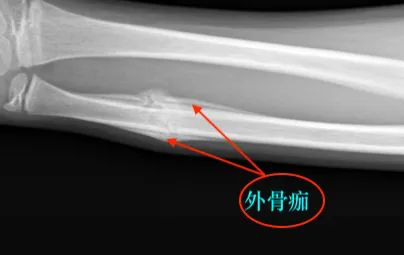

X 线片上并无明显的外骨痂形成,骨折线逐渐消失,其特征为愈合过程中无骨皮质区吸收,坏死骨在被吸收的同时由新的板层骨取代,达到皮质骨间的直接愈合。

外骨膜成骨细胞增殖,在软组织丰富区较明显,特别在肌肉附着处,因为这是骨痂血运的来源,这不难解释胫骨骨折时,前侧无外骨痂,而后侧和其他部位有外骨痂存在的原因。

当骨膜撕裂时,骨痂的增殖不能完全被纤维组织囊包围,小的新骨生成灶,有时可在周围组织甚至在肌纤维间看到,外骨痂的生成量取决于骨膜损伤程度和完整性。